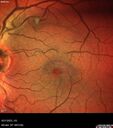

wet AMD with classic extrafoveal macular neovascularization in the good eye92 views89 year old man with longstanding vision loss in the left eye presented with one month of mild vision loss in the right eye. Vision was 20/32. This eye responded to vabysmo therapy.

wet AMD with classic extrafoveal macular neovascularization in the good eye91 views89 year old man with longstanding vision loss in the left eye presented with one month of mild vision loss in the right eye. Vision was 20/32. This eye responded to vabysmo therapy.

wet AMD with classic extrafoveal macular neovascularization in the good eye90 views89 year old man with longstanding vision loss in the left eye presented with one month of mild vision loss in the right eye. Vision was 20/32. This eye responded to vabysmo therapy.

wet AMD with classic extrafoveal macular neovascularization in the good eye89 views89 year old man with longstanding vision loss in the left eye presented with one month of mild vision loss in the right eye. Vision was 20/32. This eye responded to vabysmo therapy.